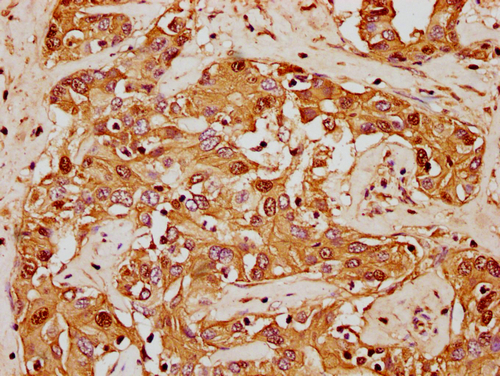

IHC image of CSB-PA010380OA62nforHU diluted at 1:20 and staining in paraffin-embedded human liver cancer performed on a Leica BondTM system. After dewaxing and hydration, antigen retrieval was mediated by high pressure in a citrate buffer (pH 6.0). Section was blocked with 10% normal goat serum 30min at RT. Then primary antibody (1% BSA) was incubated at 4°C overnight. The primary is detected by a biotinylated secondary antibody and visualized using an HRP conjugated SP system.

IHC image of CSB-PA010380OA62nforHU diluted at 1:20 and staining in paraffin-embedded human adrenal gland tissue performed on a Leica BondTM system. After dewaxing and hydration, antigen retrieval was mediated by high pressure in a citrate buffer (pH 6.0). Section was blocked with 10% normal goat serum 30min at RT. Then primary antibody (1% BSA) was incubated at 4°C overnight. The primary is detected by a biotinylated secondary antibody and visualized using an HRP conjugated SP system.